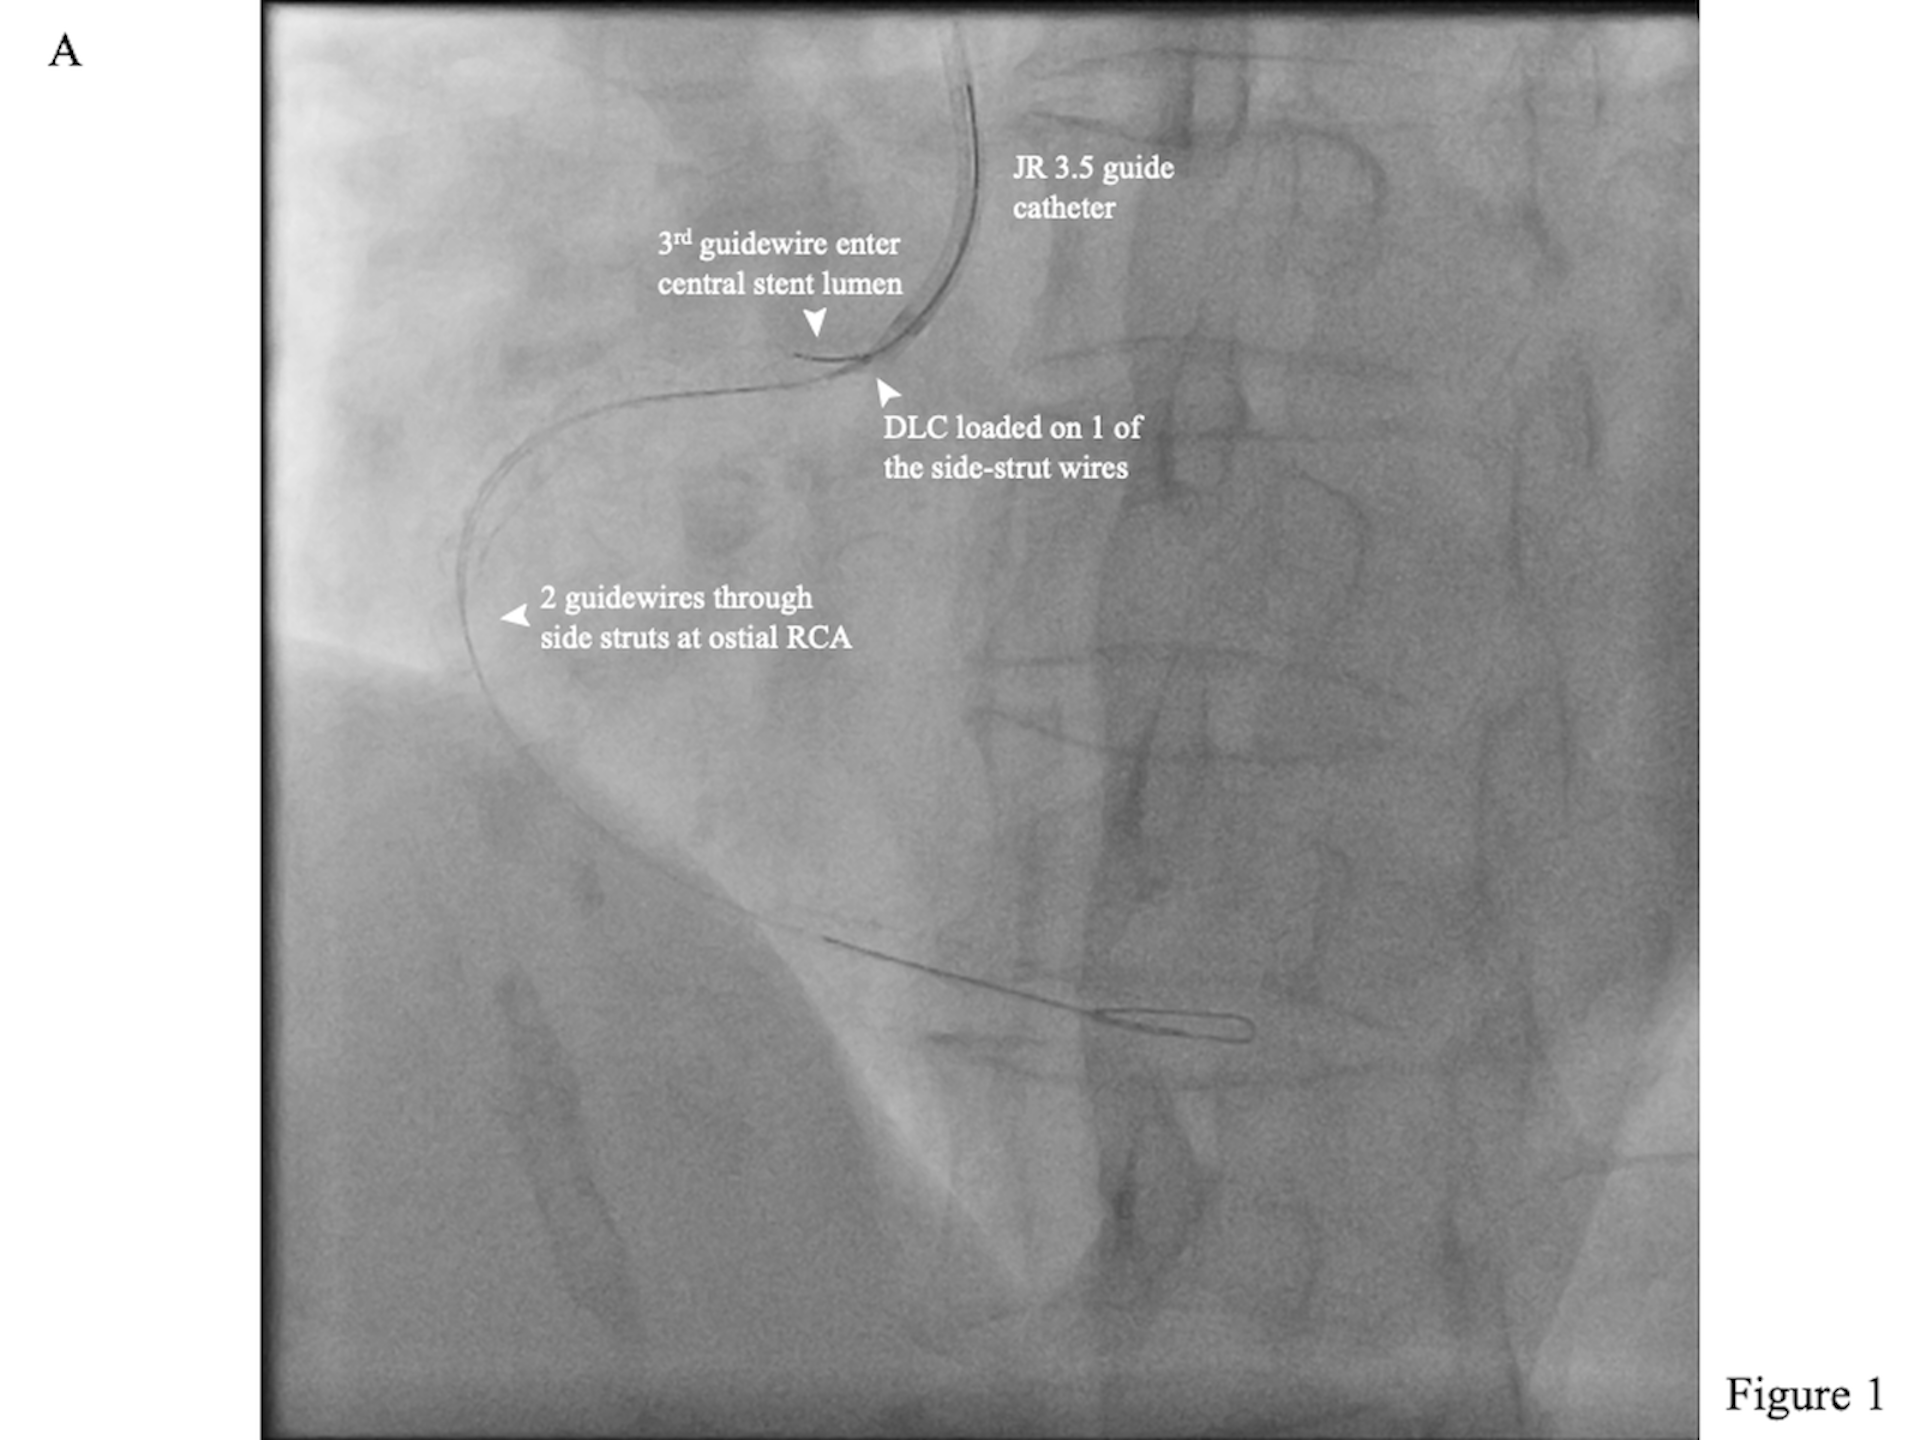

The initial rewiring entered a protruding side strut. A Sasuke dual-lumen catheter (DLC; Asahi Intecc) was inserted along the side-strut wire. The central stent lumen was then wired with another workhorse guidewire (Figure 1A, Video 1), as confirmed by intravascular ultrasound (Figure 1B, Videos 2 and 3). After post-dilatation with a 4.0-mm non-complaint balloon, the final angiographic result was good (Figure 1C, Video 4).